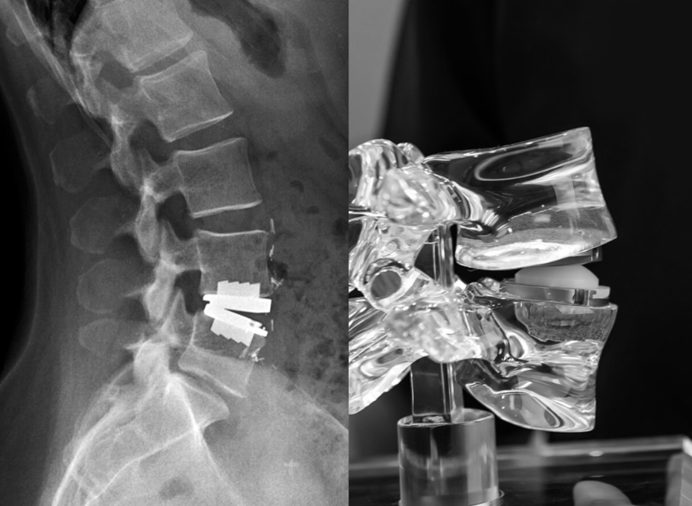

A surgery where a damaged spinal disc is removed and replaced with an artificial one that allows normal spine movement.

Artificial Disc Placement

The damaged disc is replaced with an artificial disc to maintain spine movement.

Cutting-edge technology ensures effective disc replacement with precision. Dr. Varun Khanna's expertise provides personalized treatment plans.

- Advanced surgical techniques